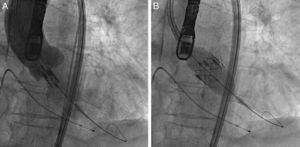

ProcedimentoO procedimento realizou-se sob anestesia geral na sala de hemodinâmica, previamente esterilizada, tendo sido o doente entubado na mesma sala na maioria dos casos. A prótese Edwards SAPIEN consiste numa válvula com três folhetos de pericárdio bovino colocada num stent metálico, expansível por balão (Figura 1). Atualmente, são comercializadas próteses de dois tamanhos: 23 (para anel valvular de 18 a 21,5mm) e 26mm (para anel valvular de 21,5 a 25mm). É implantado um eletrocateter de pace-maker provisório (via venosa femoral) no ventrículo direito e, sob estimulação ventricular rápida (∼200 lpm.), realiza-se uma valvuloplastia aórtica com balão segundo o procedimento normalizado. A implantação realiza-se por via retrógrada conforme foi previamente descrito13. Introduz-se, por dilatação sucessiva no ponto de punção, um introdutor desde a artéria femoral até chegar à aorta infrarrenal e a prótese é montada dentro do mesmo sobre um balão. O sistema avança no interior da válvula nativa e de novo sob estimulação ventricular rápida, o balão é insuflado, expandindo o stent que fica implantado ao nível do anel da válvula aórtica nativa comprimindo os véus da mesma (Figura 2). O procedimento realiza-se sob monitorização de angiografia e ecocardiografia transesofágica tridimensional. A terapia antiagregante prescrita na maior parte dos doentes foi aspirina 100mg/d e clopidogrel 75mg/d durante 3 meses.